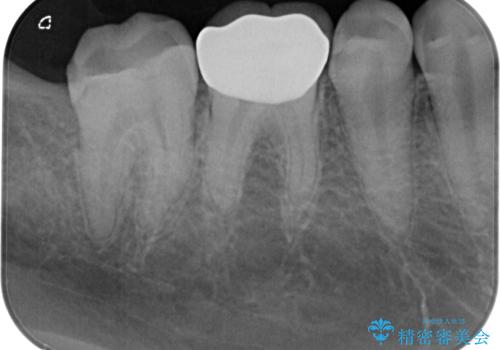

右下の6番目の歯は初診時から詰め物が大きかったため、被せものでの治療を提案していましたが、患者様の強いご希望でセラミックの詰め物(セラミックインレー)での治療をされていました。今回メインテナンス時に来院されたときに被せもの(オールセラミッククラウン)での治療を再度提案させていただき、患者様にも納得をしていただいたうえで、オールセラミッククラウンによる治療を行いました。

拡大鏡視野下で、セラミックの詰め物(セラミックインレー)、虫歯の除去を行い、オールセラミッククラウンに適した形に整えました。

歯と歯茎の間に圧排糸と言われる糸を入れてシリコーン印象材にて型どりをしました。